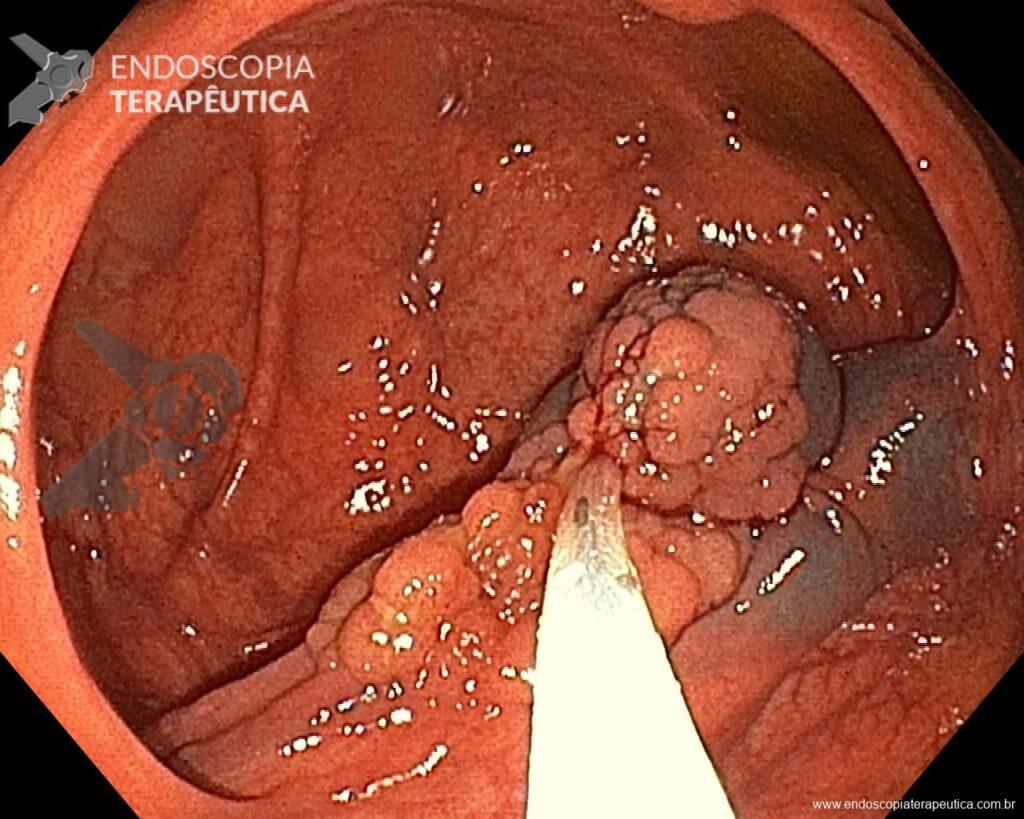

En vista de lo anterior, para el caso ejemplificado anteriormente, se optó por la resección mediante la técnica EPMR, tanto por el tipo morfológico (LST-G-H) y las características superficiales de la lesión (JNET 2A), como por su ubicación (ciego), que presenta un mayor riesgo de complicaciones.